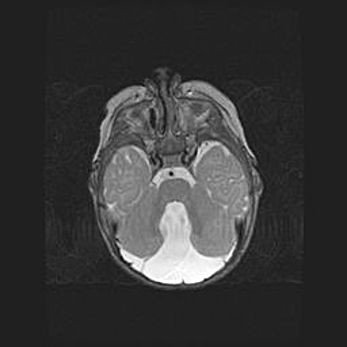

Подострая гематома правой гемисферы мозжечка.

Наружная гидроцефалия.

Возраст: 15 дней

Вес: 3100 г

Пол: женский

Окружность головы: 37 см

Срок гестации: 35-36 недель

При открытой наружной форме гидроцефалии у новорожденных расширяются и переполняются субарахноидные пространства.

Кровоизлияния в мозжечок имеют две клинико-анатомические формы: полушарные гематомы и кровоизлияния в червь.

К появлению этой патологии может привести: повреждения головного мозга, возникающие в результате асфиксии и гипоксии плода при беременности, или травмы во время родов. Редко гематома мозжечка может быть результатом первичной коагулопатии и сосудистой мальформации, диссеминированном внутрисосудистом свертывании, изоиммунной тромбоцитопении.